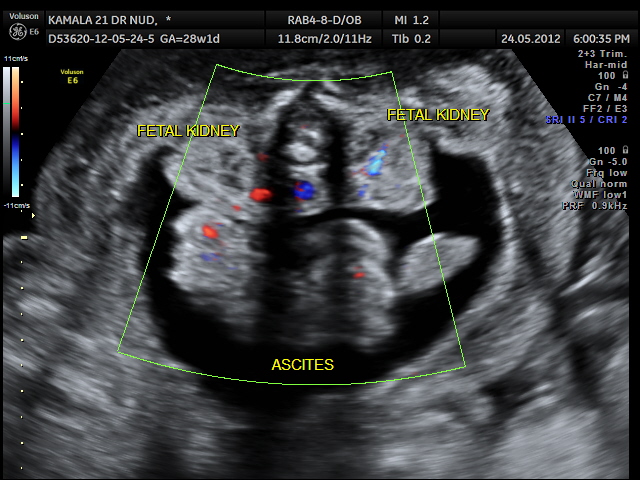

NON IMMUNE HYDROPS – RH ISO IMMUNISATION HAS BEEN RULED OUT .

THIS FETUS SHOWED SEVERE SUB CUTANEOUS EDEMA ,BILATERAL PLEURAL EFFUSION AND ASCITES .

PATHO-PHYSIOLOGY IN SHORT IS INCREASED CVP.

CAUSES COULD BE CHROMOSOMAL,CARDIOVASCULAR, PULMONARY, G.I ., G.U . ,HEMATOLOGICAL, INFECTIONS etc.